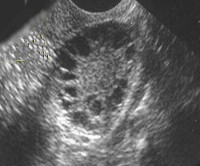

• Трансвагинальное УЗИ тазовых органов. Оба яичника обычно увеличены в размерах, имеют овальную или круглую форму. Их ткань уплотнена, выражена гиперплазия стромы. В пременопаузе фолликулы обычно смещены к периферии органа, могут отмечаться единичные кистозные изменения.